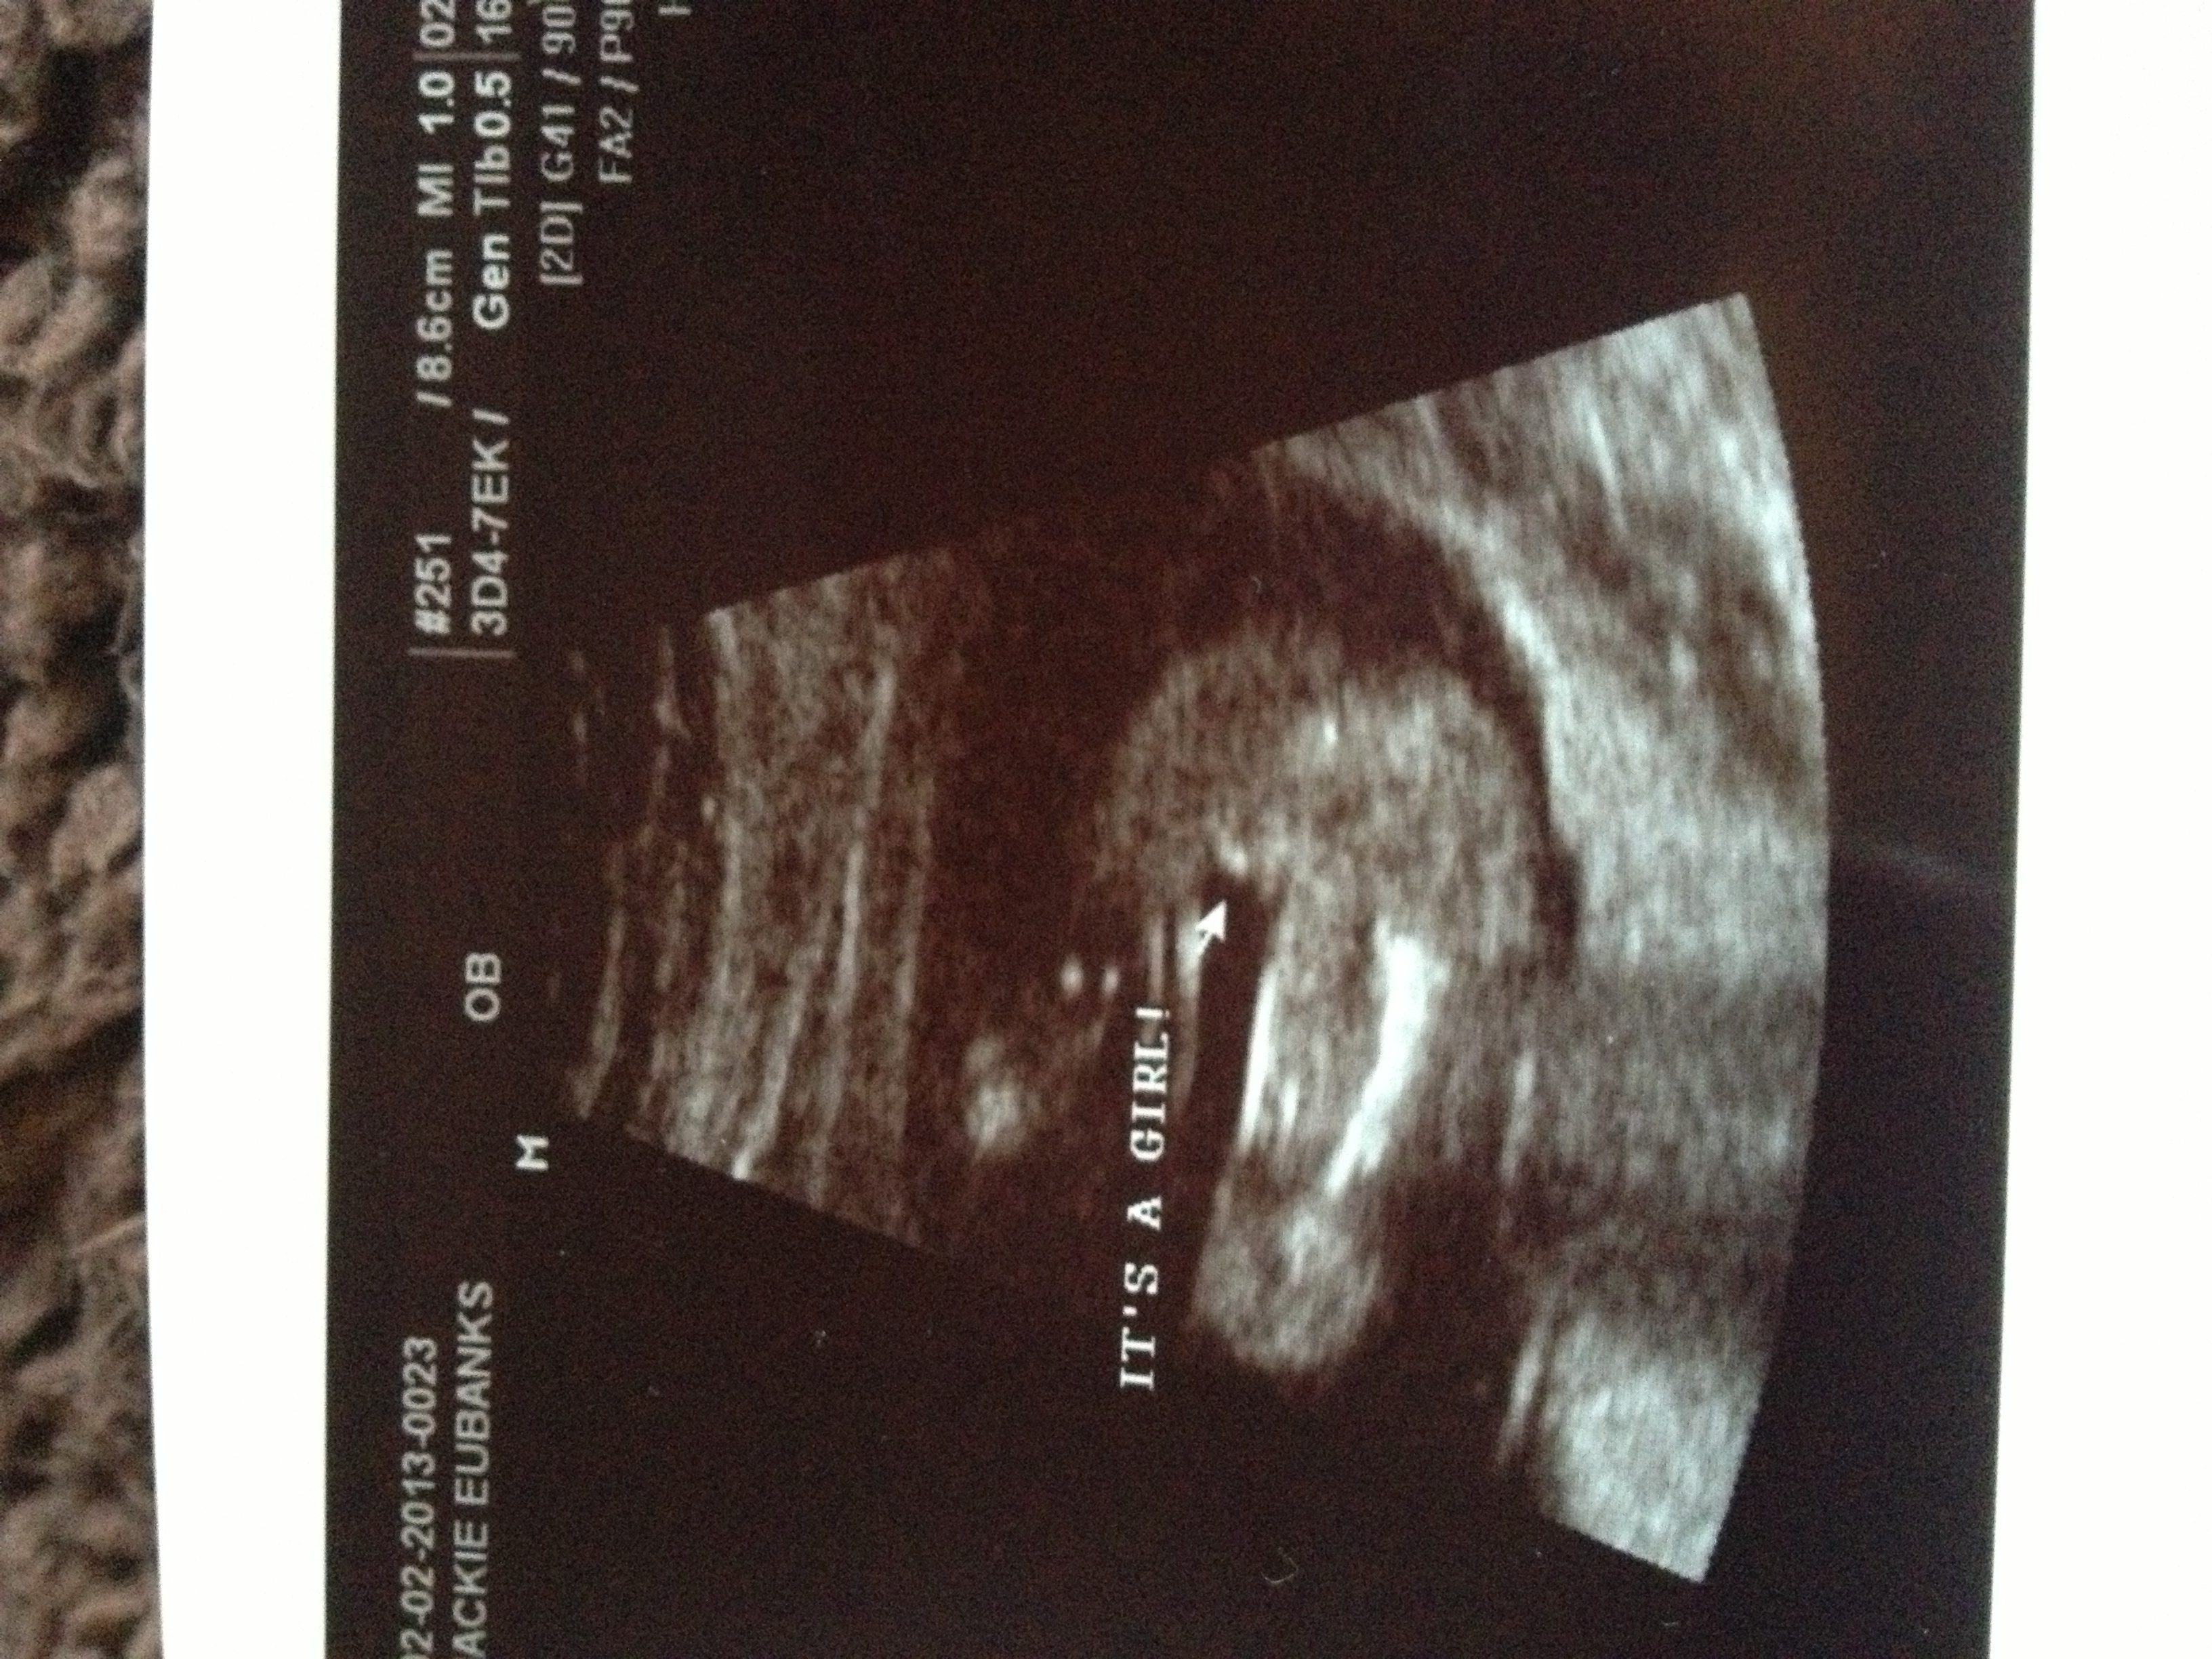

I am so excited to announce that I am expecting my 2nd child in July! My first is a boy, and I never knew about gender prediction back when I was pregnant with him! Here is my 12 week sono picture with baby number 2! Please guess away!Attachment 8048

angle looks girly, but for some reason I think boy (I don't know why.)

I think boy base on nub and skull shape.

Looks girly at the moment x

Looks girlie to me :) edited to add, your baby is dated 13 weeks makes me think girl even more

Thanks girls! I appreciate your guesses! I think girl if I had to guess. Not sure if that's a gut feeling or more bc the sonographer said 80% girl based on what she could see. @Typical_Jules.... Yeah I am actually confused on the date... They've changed my due date to a few days later, the baby was measuring about 12 weeks 3 days in these pics, although I was at time what they thought to be 13 weeks. Confusing....